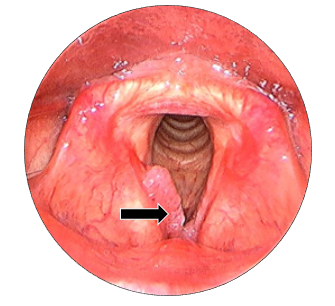

In suspension microlaryngoscopy (SML), (Figure 3) a Lindholm’s laryngoscope is used to expose the entire length of the vocal cords. External pressure can be exerted on the neck to improve the exposure of the anterior laryngeal commissure. The laser was operated using a micromanipulator coupled to an operational microscope. Using the CO2 laser set to ultrapulse mode, 100 mJ/cm2, 10 Hz repetition rate and and 250 m microspot, is used to resect the papilloma, thereby preserving the vocal ligament and normal mucosa at the anterior laryngeal commissure. The surgery is done around a small (6.5mm) endotracheal tube with the laryngoscope placed. Microlaryngoscopic view (Figure 4) showing papillomatous lesion over right true vocal fold. Following the mapping of the papillomas and photographs, cup forceps were used to obtain biopsies, which were then sent for regular pathology. Spot sizes of 0.5-0.8mm provide a comfortable compromise between depth of focus and cutting ability.

Figure 4 Microlaryngoscopic view of the true vocal folds. Black arrow: papillomatous lesion over right anterior 2/3rd aspect of vocal fold.